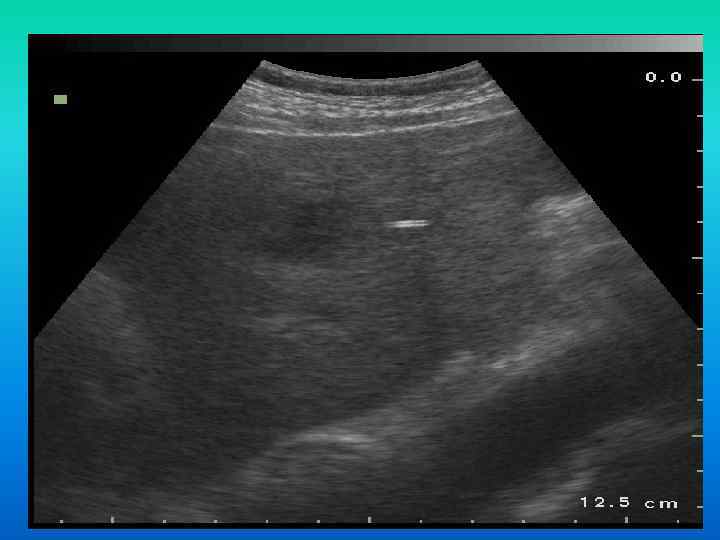

Инородное тело печени? Инородное тело печени?